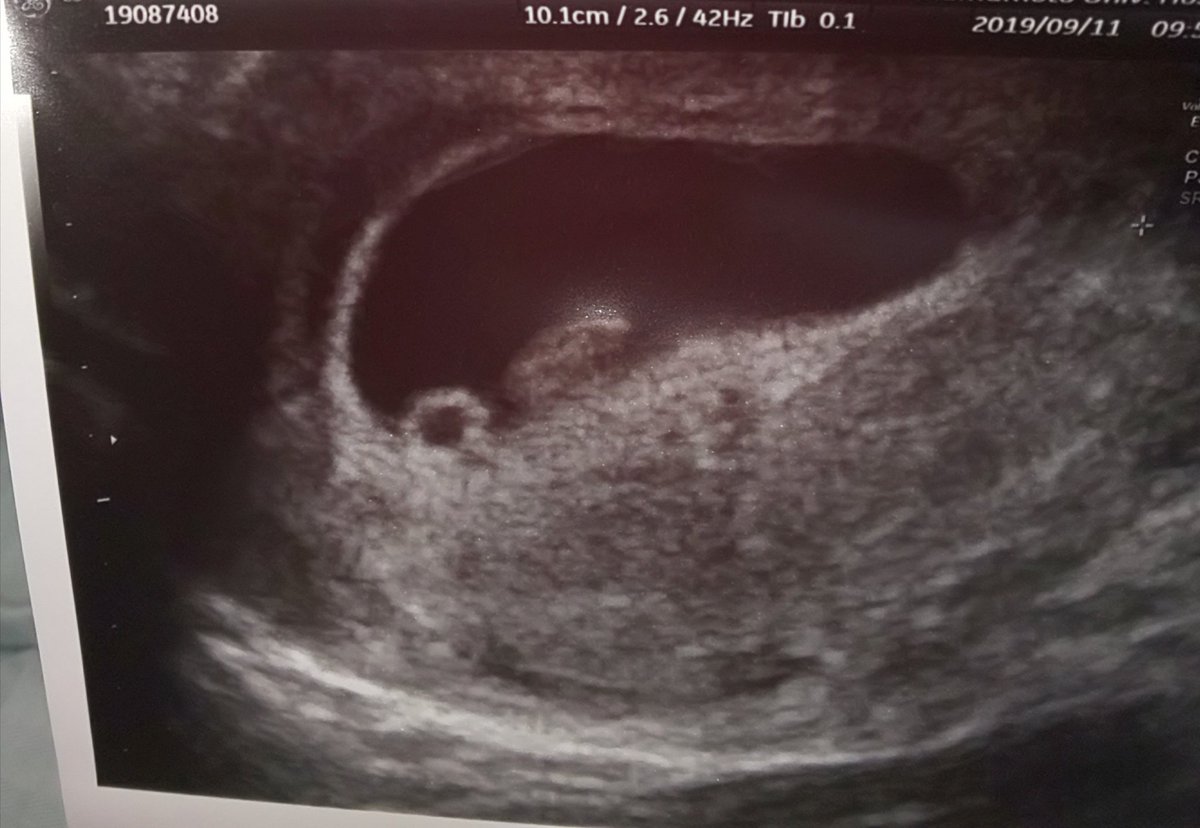

赤ちゃん241mmです。 1人目は成長遅くこの時期でやっと心拍確認出来たくらいなので、今回は順調でホッとしています( ¨̮ ) 胎嚢の下に大きめの血腫があり自宅安静中ですが、負けずに大きく育てー!!楽天市場手芸の山久の手編み > キット・セット > 赤ちゃん・子供用一覧。楽天市場は、セール商品や送料無料商品など取扱商品数が日本最大級のインターネット通販サイトAug 15, 19 · エコーで見る赤ちゃんは217mmとごくごく順調に育っています。 胎嚢も育ってはいるのですが、やはりネットで出てくる9wのエコーと比較してしまうと、まぁ赤ちゃんが窮屈そうで。

妊娠9週1日 9w1d の超音波 エコー 写真